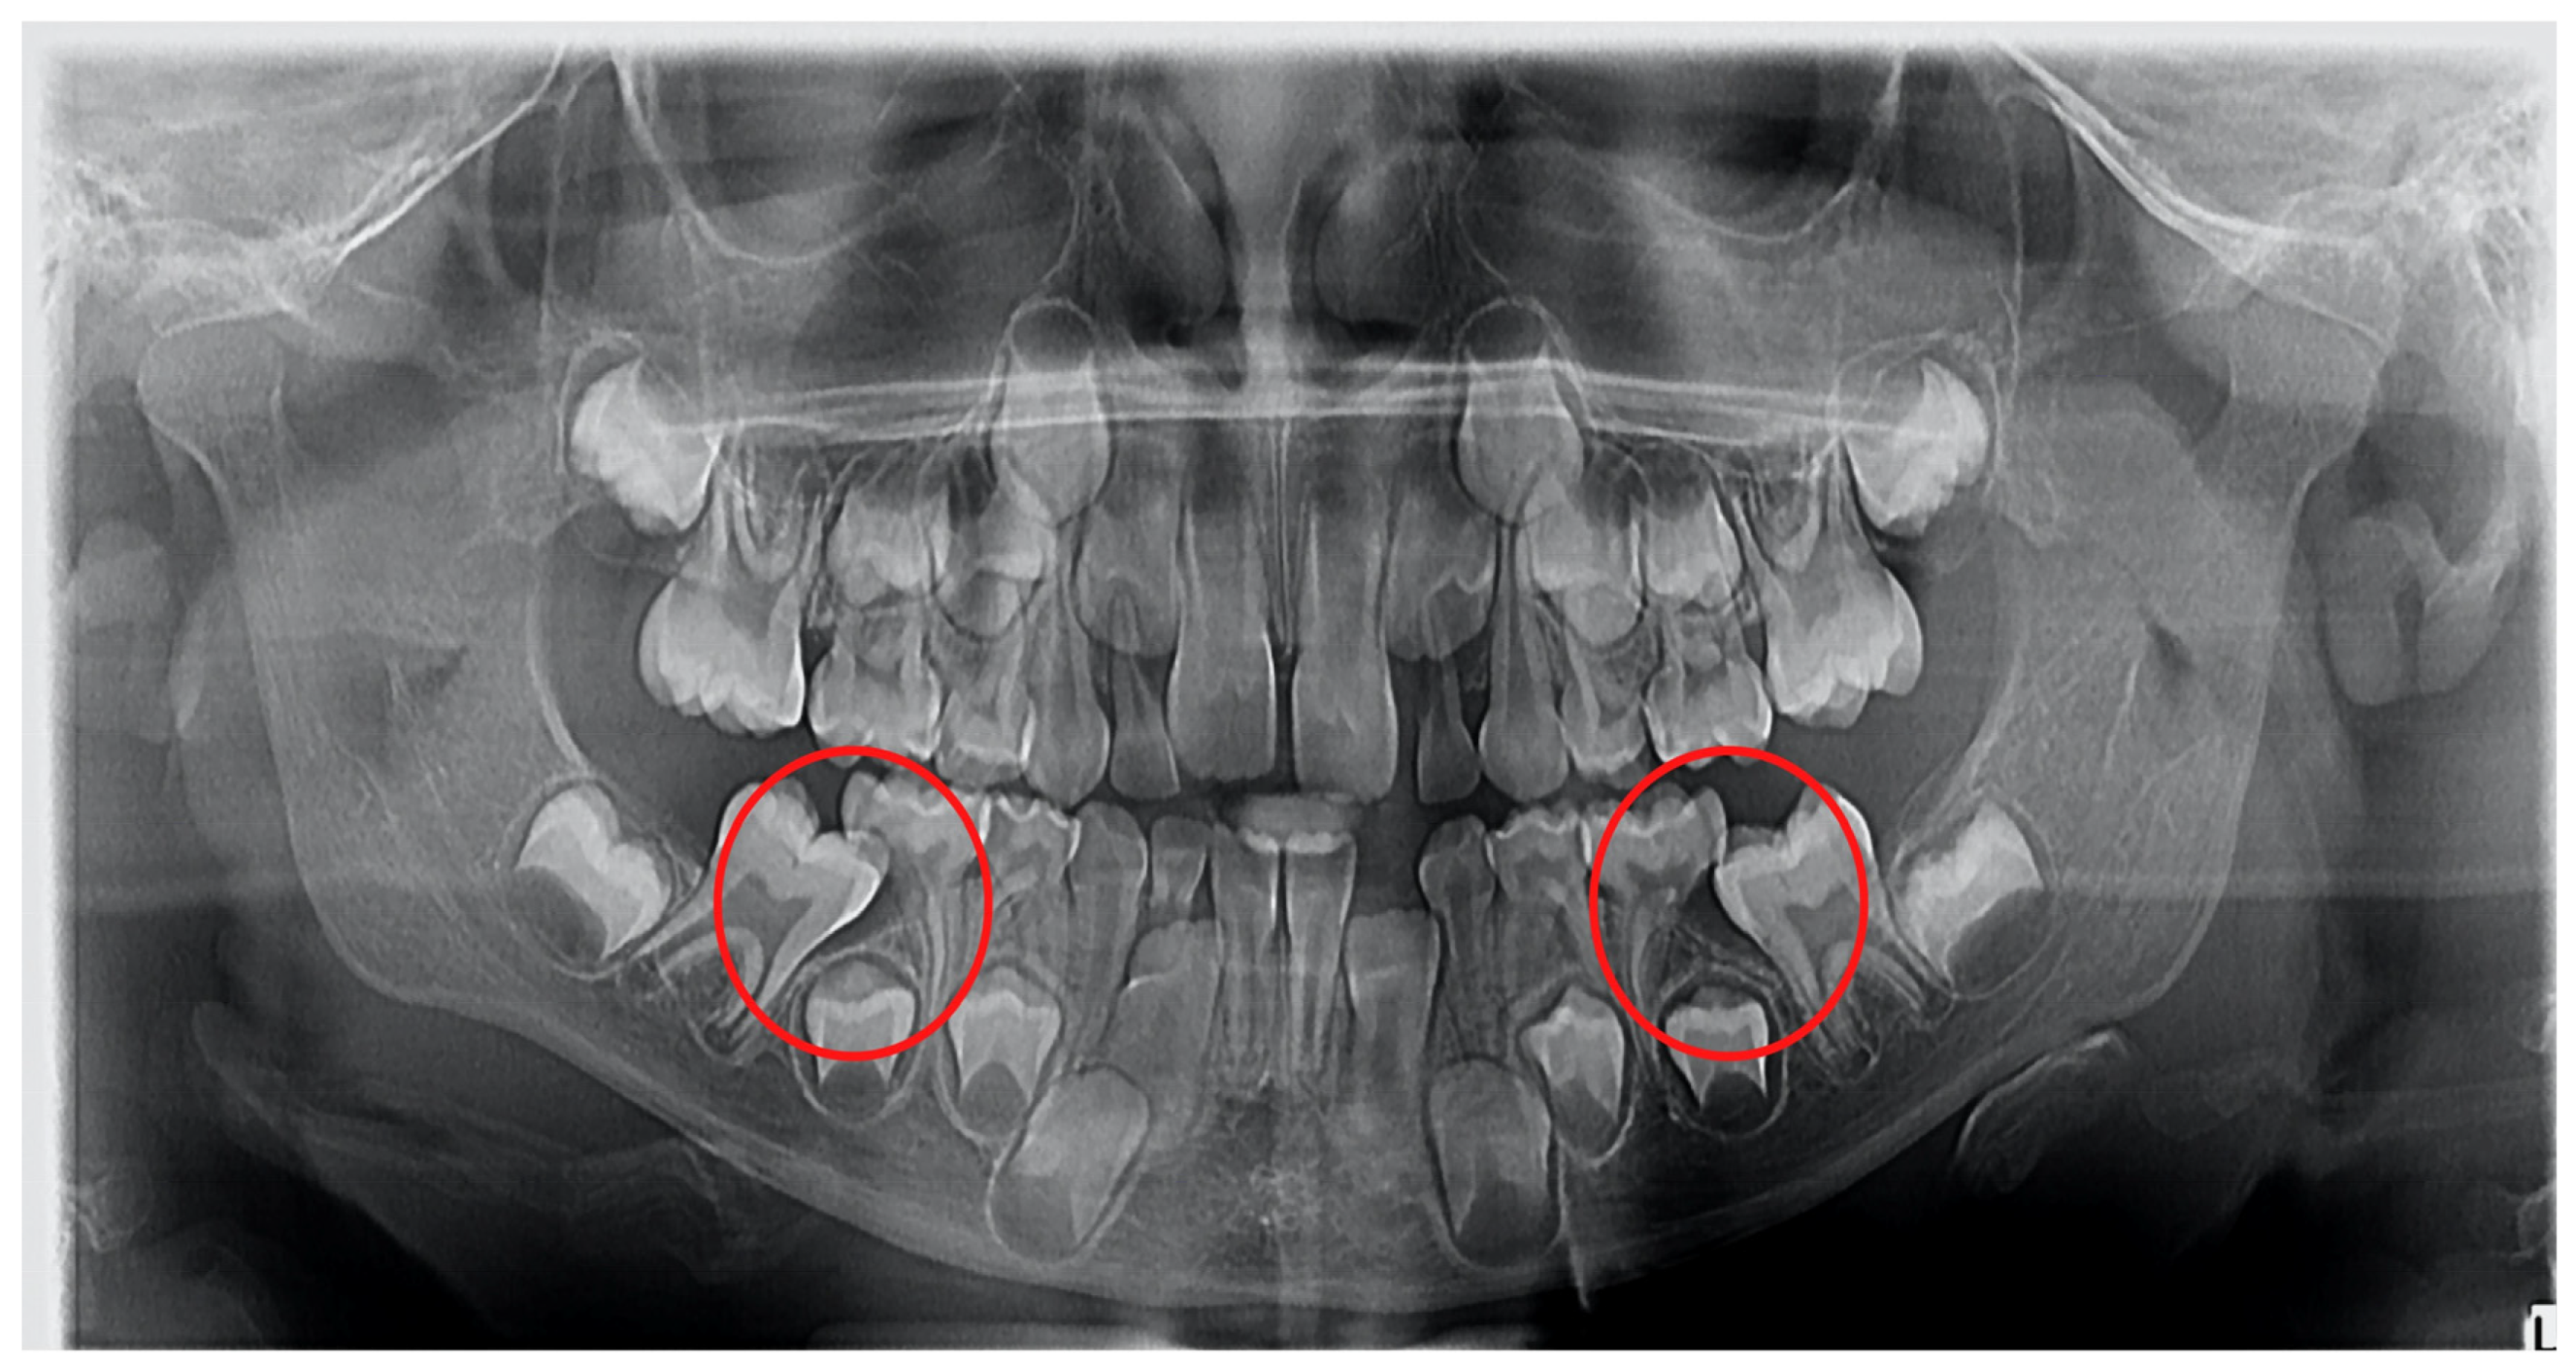

1. Introduction

2. Materials and Methods

2.3. Radiological Examination